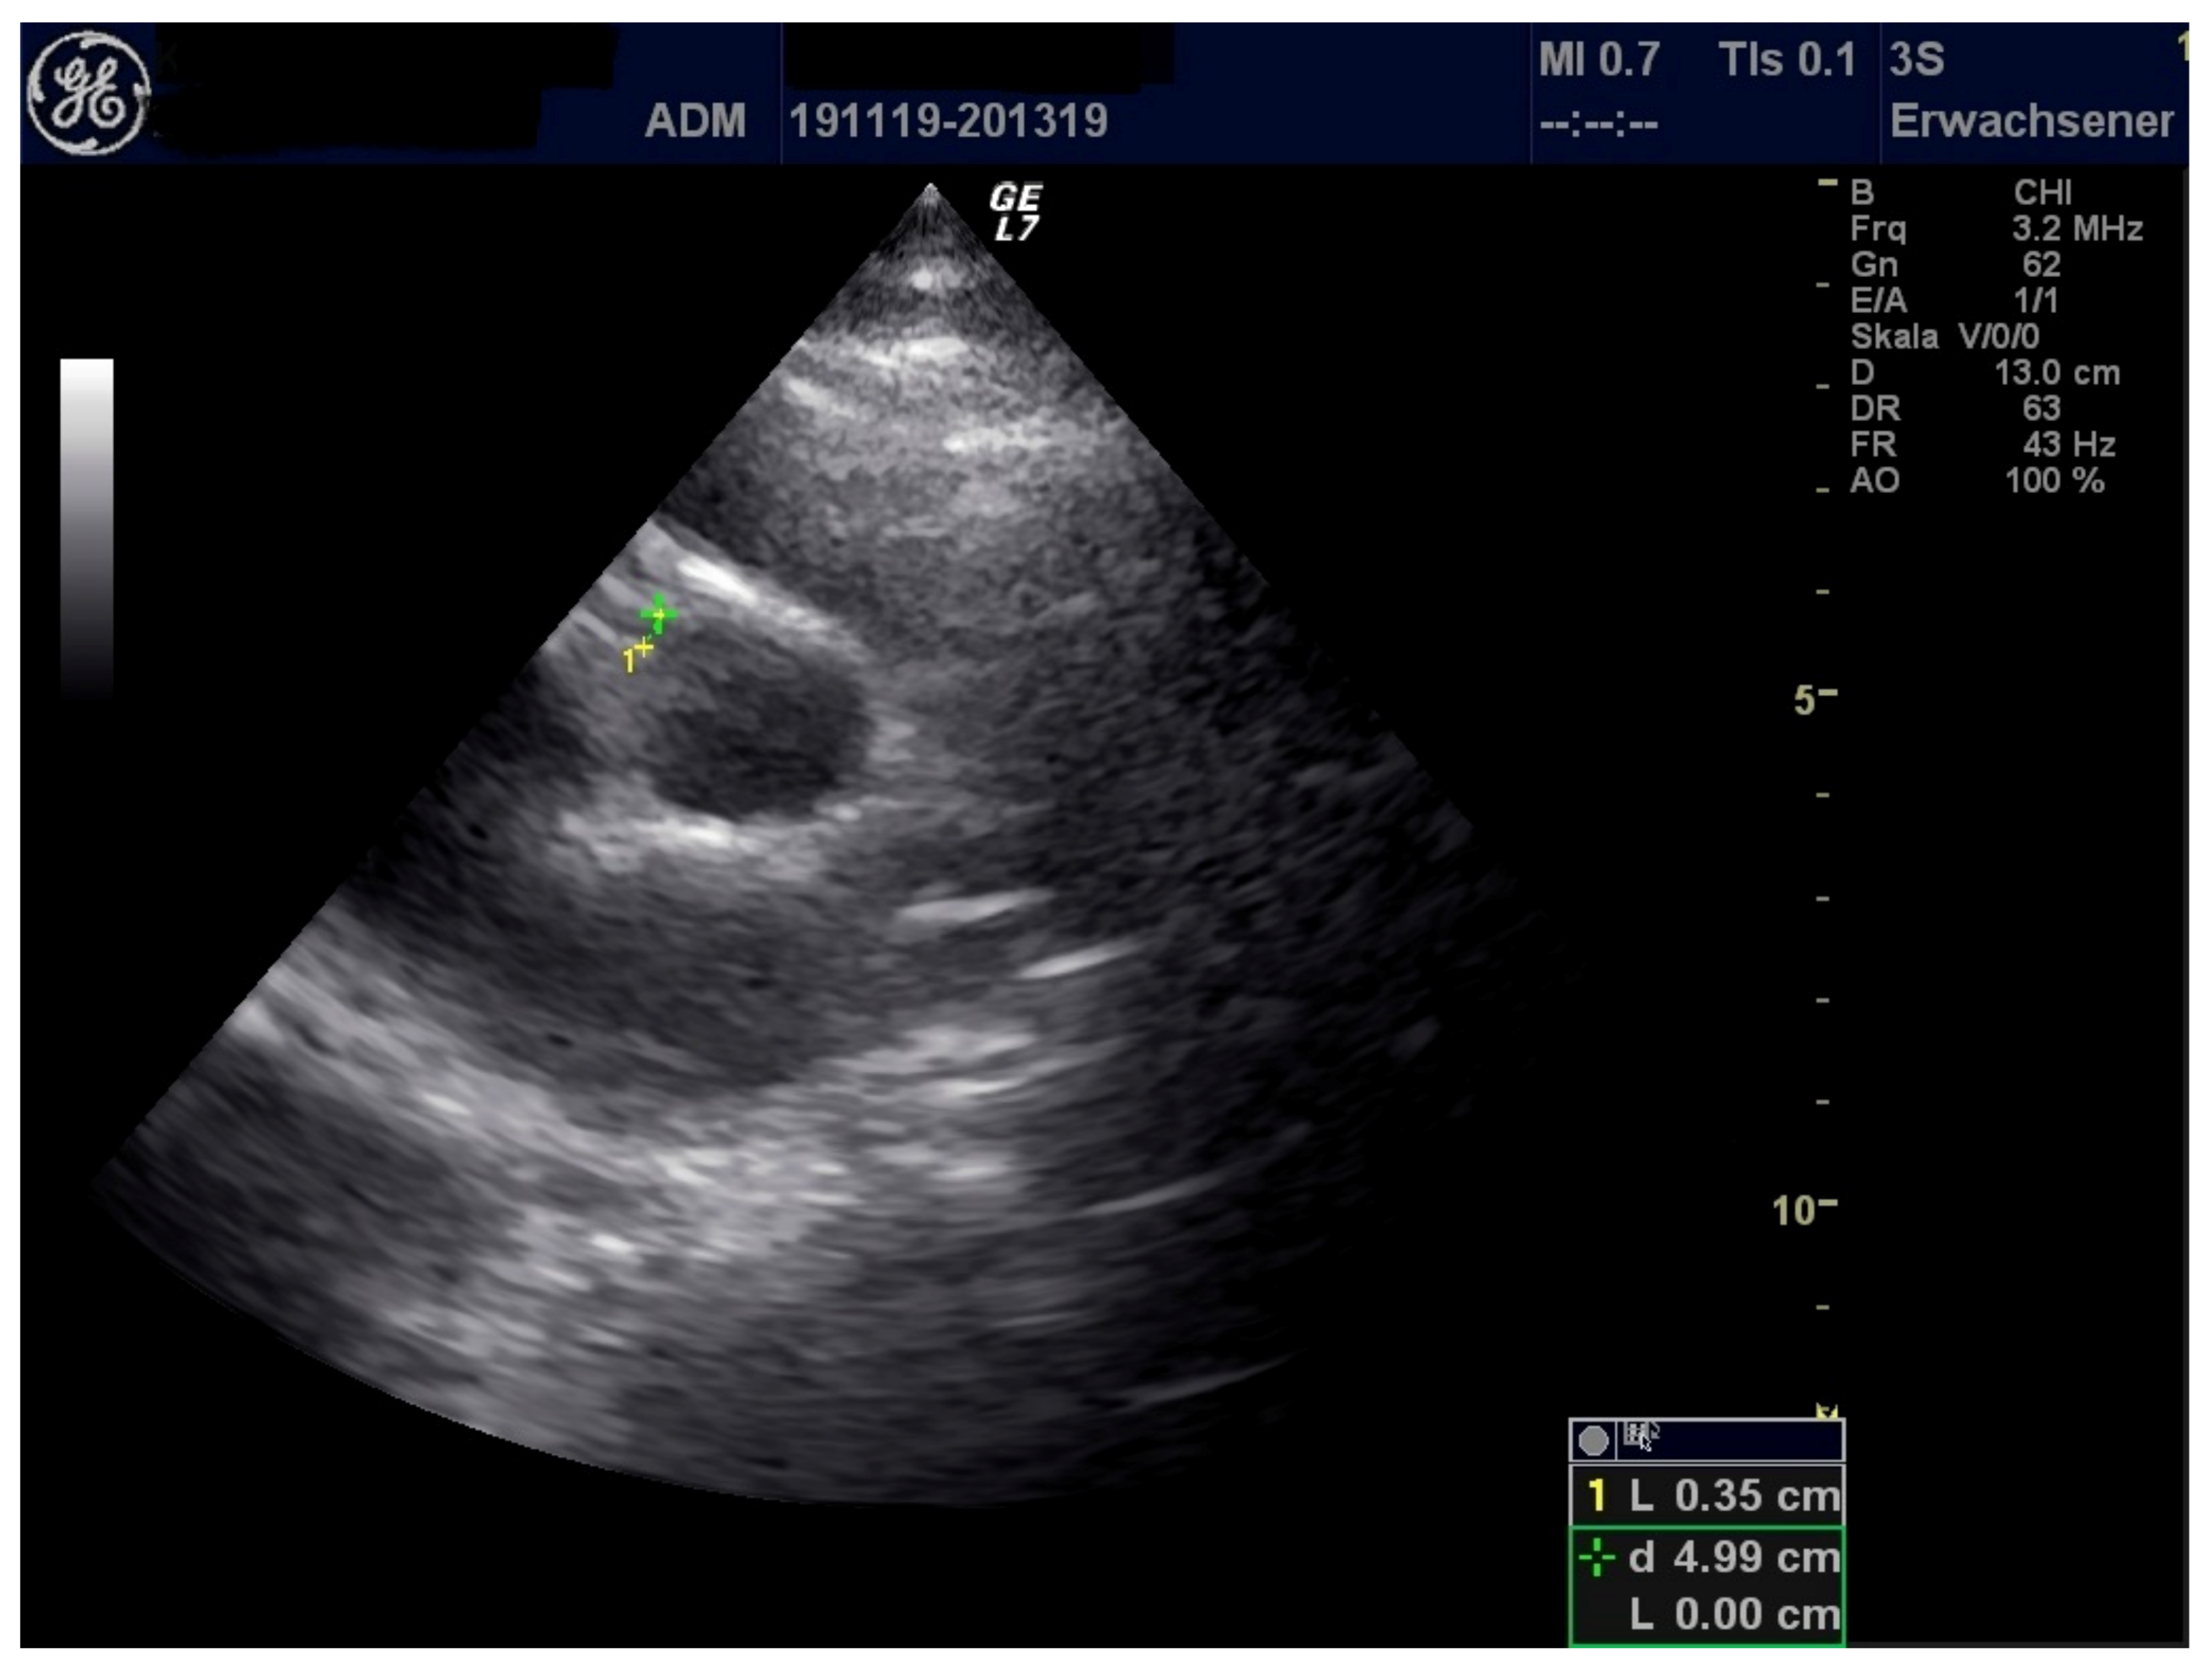

| LVEF (%) | 71 | 44 | 53 |

| FS (%) | 40 | 21.1 | 26.6 |

| MAPSE (cm) | 1.97 | 1.42 | 0.91 |

| TAPSE (cm) | 2.55 | 2.08 | 1.14 |

| LCA (mm) | 3.8 | 3.3 | 3.1 |

| RCA (mm) | 3.2 | 4.0 | 2.8 |

| Pericardial effusion (mm) | 7 | 3 | 5 |

| Pleural effusion (mm) | 9 (left), right 0 | 0 | 0 |